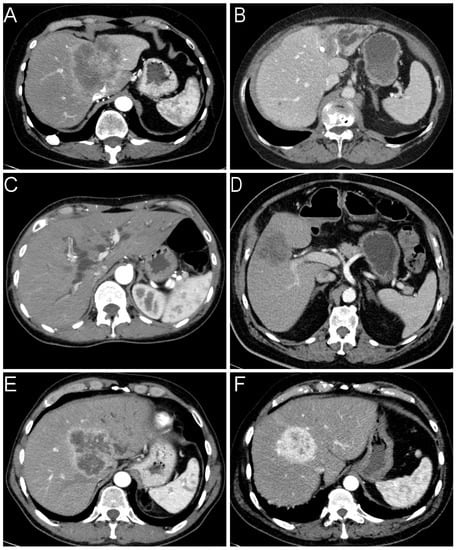

Small and large duct iCCAs differed significantly in several histopathological characteristics (see Table 3 and Figure 2). Biliary intraepithelial Neoplasia (BilIn) and intraductal papillary neoplasms of the bile ducts (IPNB) were only diagnosed in large duct iCCAs. We observed mucin formation in 82% of large and only 12% of small duct iCCAs. A periductal-infiltrating (PI) growth was mainly found in large duct iCCAs (57% compared to 3%). However, due to the correlation between the presence of a precursor lesion and a PI growth pattern (rS = 0.706, p < 0.001), the PI growth pattern was not an independent variable. Consequently, the growth pattern was not included in the regression analysis. Nevertheless, univariate analysis of growth patterns showed the third-highest effect size after the detection of precursor lesions and the production of mucin. A graphical representation of the difference in growth patterns is illustrated in Appendix A, Figure A1. Histological evidence of a desmoplastic stromal reaction, lymphangioinvasion and corresponding metastases, as well as perineural invasion showed considerably lower effect sizes. Those factors were more likely present in large duct iCCAs but sometimes diagnosed in small duct iCCAs, too.

Figure 2.

Histological distinction features of iCCA. (A) Adenocarcinoma forming solid sheets; (B) with cuboidal cells; (C) Infiltrative glands composed of prismatic cells. Different histological growth patterns of iCCA showing (D) a mass-forming (MF) tumor, (E) a tumor showing intraductal growth (IG), and (F) a tumor with periductal-infiltrating growth. Note the adjacent inconspicuous biliary epithelium (inlay; (E,F)). (G) Biliary intraepithelial neoplasia of low-grade and (H), 200X magnification) high-grade; (I) intraductal papillary neoplasm of the bile ducts. Different amounts of mucin: (J) little mucin with PAS-positivity showing in the inlaid picture; (K) moderate and (L) extensive amounts of mucin. (M) Lymphangioinvasion and (N) lymph node metastasis. (O) Perineural invasion.

Taking into account the frequency of liver lesions, studies involving comprehensive clinicopathologic investigations on the differential diagnoses are of special importance. Apart from the frequent benign liver hemangioma, rare cases of hepatocellular adenoma and focal nodular hyperplasia, primary and secondary malignancies need to be ruled out. In addition to iCCAs, also hepatocellular carcinomas (HCCs) are primary liver carcinomas with characteristic clinical and radiologic features distinguishing both entities. The hepatocellular origin of a tumor may already be distinguished conventionally and morphologically by routine histopathology together with typical radiologic features and clinical context, as HCCs are most frequently associated with liver cirrhosis. In particularly difficult cases, as for certain types of HCCs as well as combined hepatocellular-cholangiocarcinoma (HCC-CCC), the diagnosis needs further immunohistochemical analyses such as Hepatocyte paraffin 1 (HepPar1) [24]. So far, the final histopathologic diagnosis of iCCA including its subtype is necessary for further therapy planning, even in unresectable cases [25]. Tumor biologic heterogeneity is reflected in the new classification of subtypes, which incorporates a large number of different diagnostic factors. The exact determination of iCCA subtypes is not only the basis for further studies but also for the individual patient prognosis and therapeutic regimens. For these reasons, one of the central goals of the European Cholangiocarcinoma Network is to determine factors important for subtyping [26]. Numerous features have already been identified that distinguish iCCA subtypes on a histologic basis. These characteristic histologic features include precursor lesions [27,28], growth patterns [29], perineural invasion and lymph node metastases [30], stromal desmoplasia, and mucin [8]. In our analyses, we demonstrated that some factors outclass others in iCCA subtype differentiation. Precursor lesions were found exclusively in large duct iCCAs and mucin production was negative in 88% of small duct iCCAs compared with the 18% in large duct iCCAs. In addition, we were able to show that not only the macroscopic growth pattern—which may not even be known—but also the microscopic growth pattern may significantly help iCCA subtyping. The strong correlation between a periductal-infiltrating growth pattern and the detection of precursor lesions suggests a direct relationship. It may be assumed that bile ducts with BilIns high grade act as origin of the invasive carcinoma outgrowth. In some cases, however, no precursor lesion may be seen, as the bile duct, from which the invasive carcinoma originates, has been completely consumed. As large bile ducts and peribiliary glands often produce mucin, also large duct iCCAs may produce mucin in contrast to small duct iCCAs [31]. An iCCA that does not show a precursor lesion, mucin production, or a periductal-infiltrating pattern can only be designated as a large duct iCCA by a combination of several other histological criteria. Factors such as stromal desmoplasia, lymphangioinvasion, and lymph node metastases, especially in the case of small tumors, perineural infiltration, and a central location should then be considered. In these cases, it would also be advisable to determine the diagnosis conclusively only in the context of an interdisciplinary tumor board. In rare cases, the classification into the iCCA subtypes was difficult as some borderline cases showed properties of both entities, possibly representing a kind of intermediate duct iCCA. For the sake of this study, we assigned the specific subtype for which they presented the most characteristic features, although not all characteristics were fulfilled.